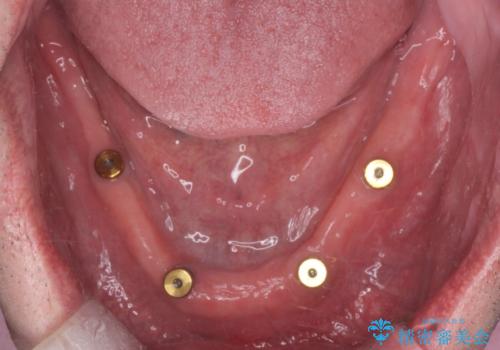

保存できる歯がなかったので全て抜歯をし、インプラントを埋入し、磁性アタッチメントを用いたインプラントオーバーデンチャーで治療を行いました。

- 350万円(インプラント・マグネットアバットメント×8・金属床義歯・骨造成・静脈内鎮静麻酔)費用は治療当時の料金となります